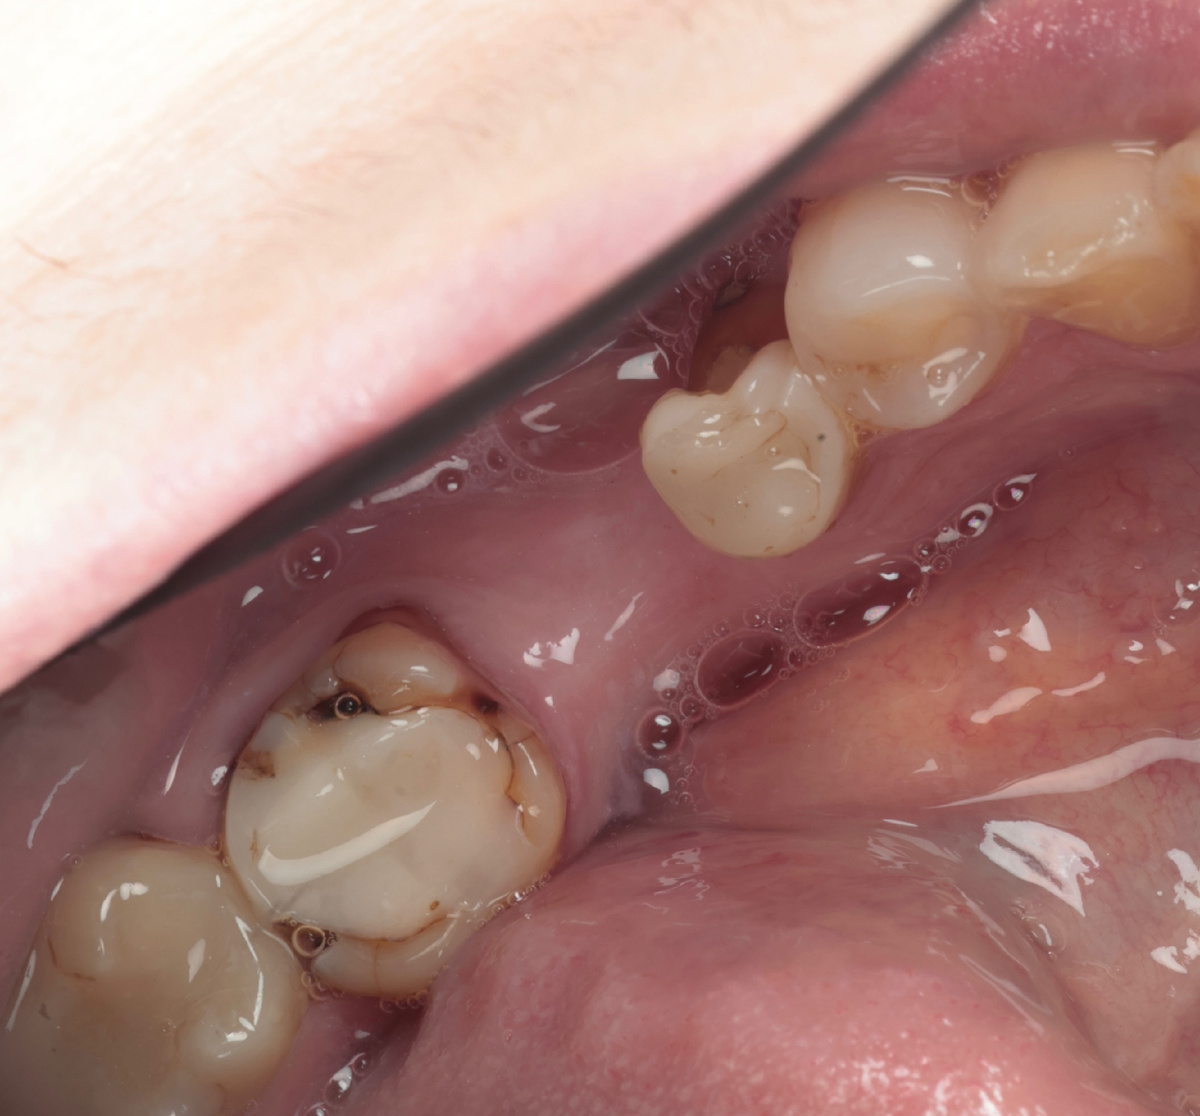

Смотрим на фотографию, с этого ракурса ещё ничего:

Семёрка - под обширной дефектной пломбой, шестёрка отсутствует, пятёрка имеет значительный скол пломбы со щёчной стороны. Вот этот ракурс уже интереснее выглядит: